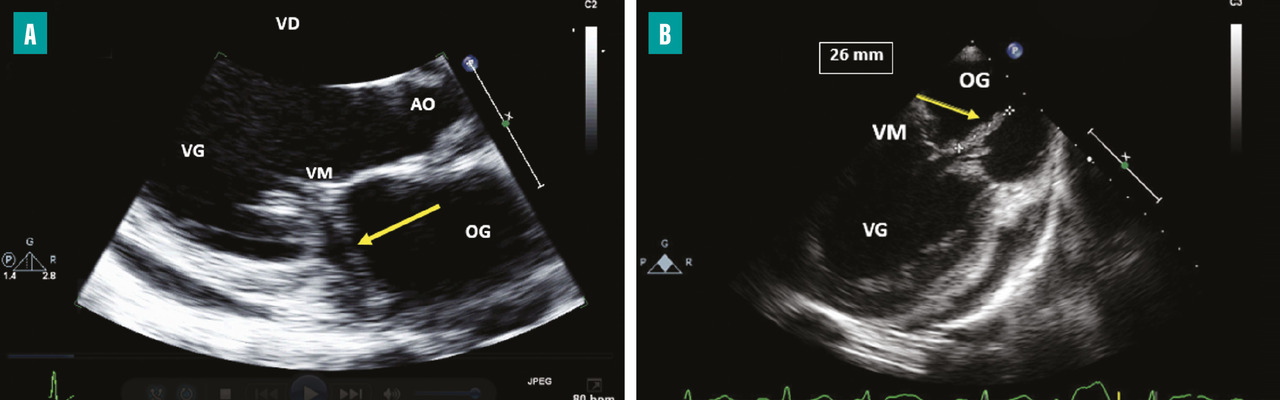

L’apparition à l’échographie cardiaque d’un abcès périvalvulaire ou périprothétique aortique (fig. 3 ) ou mitral est une complication grave de l’EI. L’abcès est plus fréquent dans les EI sur prothèses valvulaires (50 à 80 % contre 10 à 40 % sur valves natives). L’ETO est plus sensible que l’ETT pour ce diagnostic (notamment pour les localisations postérieures)2 et le scanner cardiaque est très performant pour la recherche d’abcès sur prothèse. La détersion de l’abcès peut être à l’origine de fistules entre les différentes cavités cardiaques (fig. 4 ). La fistulisation se fait le plus souvent dans la chambre de chasse du ventricule gauche. Les fistules intracardiaques dans l’oreillette gauche ou droite peuvent être à l’origine d’un tableau d’insuffisance cardiaque et compliquent le geste chirurgical.

– à l’évolution locale de l’infection par une extension périvalvulaire ou périprothétique des lésions et la formation d’un abcès (fig. 3 ) ou d’une fistule intracardiaque (fig. 4 ).

En cas de sepsis non contrôlé, il est impératif de refaire des hémocultures, de réaliser une surveillance rapprochée en ETT et en ETO, à la recherche d’un abcès périvalvulaire ou périprothétique. Un scanner thoraco-abdomino-pelvien et cérébral ou un TEP-scan est demandé, à la recherche d’un foyer infectieux embolique.

– une évolution de l’infection locale avec un abcès périvalvulaire ou périprothétique, l’apparition d’un faux anévrysme ou d’une fistule intracardiaque, une augmentation de la taille des végétations sous traitement antibiotique adapté, des signes de désinsertion de prothèse ou la survenue d’un bloc auriculoventriculaire (recommandation de classe IB) ;